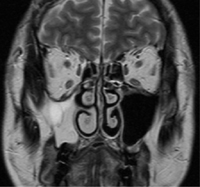

MRI

右上顎洞の炎症所見

積極的に腫瘍性病変を示す所見なし

高タンパク内容を反映する信号強度

MRIT2強調冠状断像